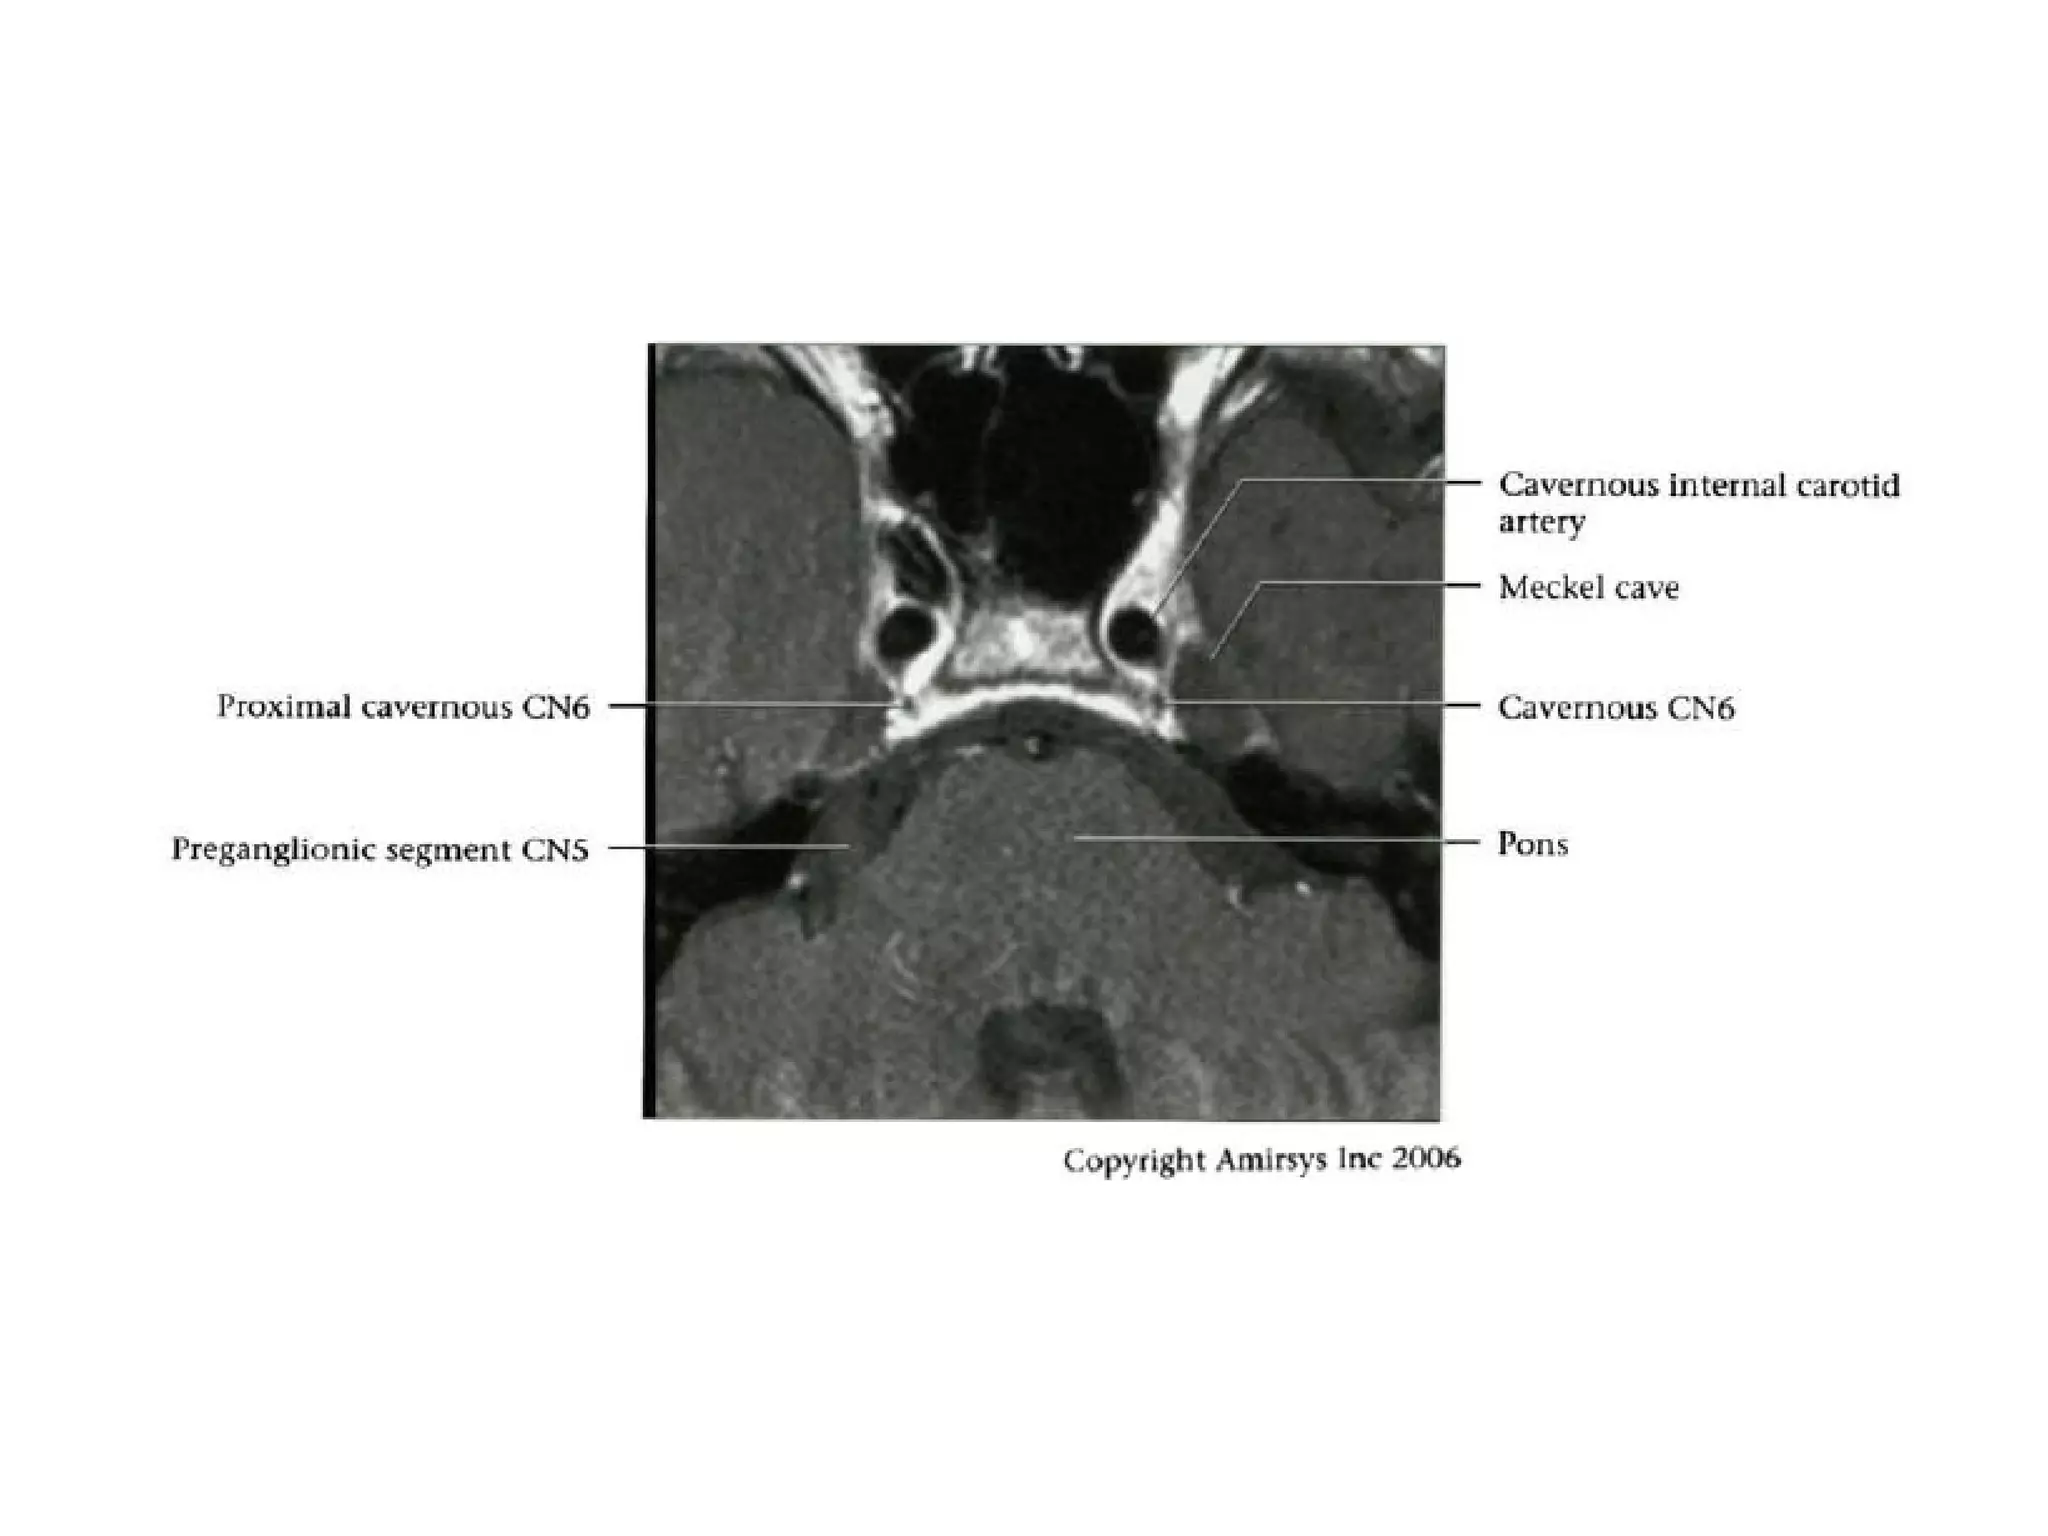

CN6CN6

Abducens nerve

Overview

• Sixth cranial nerve

• Motor nerve to lateral rectus muscle only

• CN6 is a pure motor nerve

• Five segments can be defined: Intra-axial,

cisternal, interdural, cavernous and

extracranial (intra-orbital)

Cisternal Segment

• CN6 ascends anterosuperiorly in

prepontine cistern toward site where it

penetrates dura

• May be posterior or anterior to anterior

inferior cerebellar artery

• Penetrates dura of basisphenoid to enter

Dorello canal

Interdural Segment

• Dorello canal represents channel within basilar venous plexus

(petroclival venous confluence)

- Channel is located between two layers of dura

- Basilar venous plexus is continuous with cavernous sinus

anteriorly

- Basilar venous plexus drains into inferior petrosal sinus

• Extends from point where CN6 pierces inner (cerebral) layer dura

mater to its entrance into cavernous sinus

• Within Dorello canal, abducens nerve is surrounded by layer of

arachnoid mater & occasionally dura mater

• After penetrating dura, CN6 passes superiorly through basilar

venous plexus

- It then arches over petrous apex below petrosphenoidalligament

into upper posterior region of cavernous sinus

- Bony sulcus of CN6 as it passes over top of petrous apex usually

present

Cavernous Segment

• CN6 courses anteriorly within cavernous sinus

- Abducens nerve is only cranial nerve to lie

within cavernous sinus

- Cranial nerves 3, 4, VI and V2 are all

embedded within lateral wall of cavernous sinus

• Within cavernous sinus CN6 runs along

inferolateral aspect of cavernous internal carotid

artery

Cranial Nerve VI:

The Abducens Nerve

• The abducens nerve emerges from nuclei anterior to the

fourth ventricle, then courses anteriorly through the pons

to the pontomedullary junction and into the prepontine

cistern.

• After crossing the prepontine cistern in a posterior-to-

anterior direction, the abducens nerve runs vertically

along the posterior aspect of the clivus, within a fibrous

sheath called the Dorello canal.

• The nerve then continues over the medial petrous apex

and through the medial cavernous sinus, entering the

orbit through the superior orbital fissure to innervate the

lateral rectus muscle.

RadioGraphics 2009; 29:1045–1055

• It is important to note that the abducens nerve

runs almost the entire length of the clivus.

• Radiologists should be vigilant for clivus and

petrous apex abnormalities in the setting of

abducens nerve palsy.

• Although the abducens nerve lies near the

anterior inferior cerebellar artery and has a

similar caliber, the two structures course in

orthogonal directions and are thus easily

distinguished.